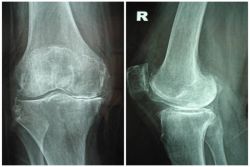

Hội thấp khớp học Hoa Kỳ (American College of Rheumatology, ARC) đã đưa ra một số tiêu chuẩn để chẩn đoán chính xác thoái hóa khớp gối. Những biểu hiện của thoái hóa khớp gối bao gồm: xuất hiện gai xương dưới sụn, mất dần sụn khớp, xơ hóa xương dưới sụn, cử động khớp đau, có tiếng lục khục, lệch trục khớp...

X-quang có vai trò quan trọng trong chẩn đoán các bệnh lý khớp gối. Nó là một trong những xét nghiệm nằm trong tiêu chuẩn chẩn đoán bệnh và dùng phân biệt giữa các bệnh lý khớp gối khác nhau.